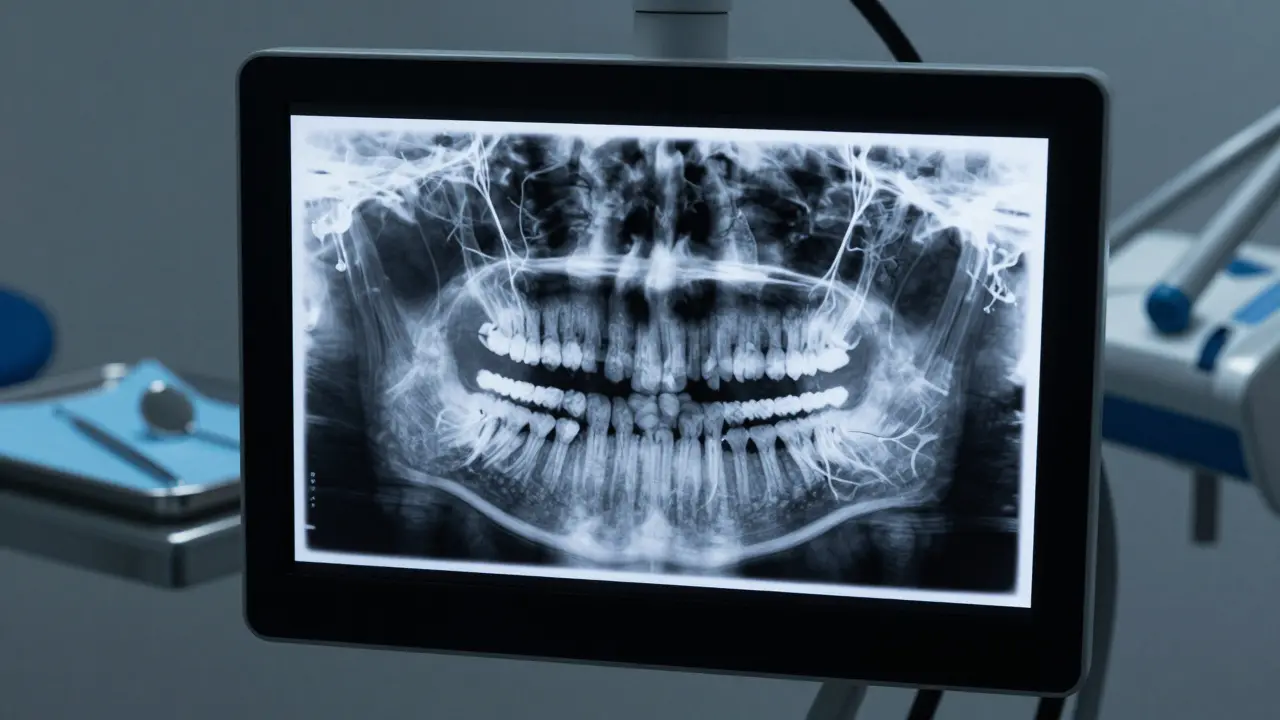

Dentální rentgenový snímek ukazující detailní strukturu kořenů zubu.

Zajímavosti z pohledu rentgenu

Protože kořeny nevidíme, používáme dentální rentgen je diagnostický nástroj využívající X-záření k vizualizaci tvrdých tkání zubu a stavu kosty. Pomocí něj vidíme, zda je kořen přímý, nebo zda má anomálie, jako je například zakřivení (dilacerace).

Někdy se stává, že zuby mají tzv. fúzované kořeny, kdy dva kořeny u jednoho zubu splynuly v jeden. To není nemoc, ale vrozená anatomická variace. Pro zubáře je to ale důležité vědět, zejména pokud plánuje extrakci zubu, aby neznepomohl v odtahu.